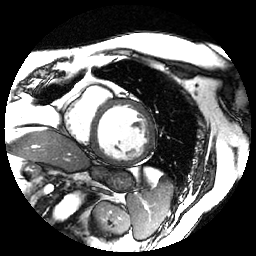

The Figure 1 below shows an example of an input image, the inferred region of interest (ROI), corresponding to the manually delineated contours.

From one original MRI image and its corresponding contour (provided as a list of coordinates of every point of the contour), we have to compute binary masks. We use the previous as inputs to our combined approach. An example is shown in Figure 2.